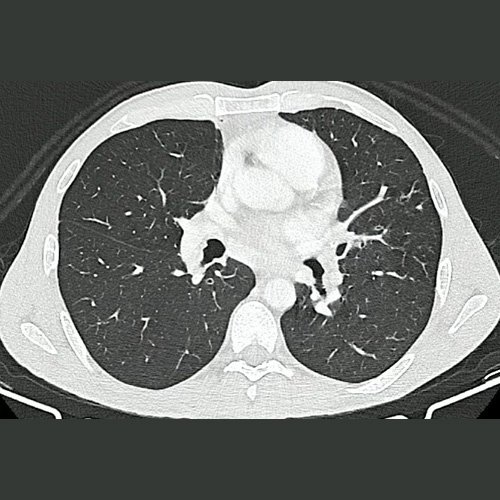

• TAC de tórax con contraste EV (DÍA 1): Persiste adenopatía mediastinal subcarinal de 16 mm de diámetro en su eje corto. El resto de los ganglios mediastinales visibles son de tamaño y morfología normal. El árbol traqueobronquial no presenta alteraciones. El análisis del parénquima pulmonar muestra múltiples pequeñas bronquiectasias de paredes gruesas, asociadas a discreto patrón de árbol en brote y a pequeñas atelectasias laminares subsegmentarias, en segmento anterior del lóbulo superior derecho, lóbulo medio, segmentos lingulares, y segmentos basales de ambos lóbulos inferiores. Hallazgos ya presentes en estudio anterior.

Tomografía de tórax (Ventana pulmonar-corte axial) DÍA 1

• TAC de tórax sin contraste (31/03/2025): adenopatías mediastinales subcarinales de 16mm. Múltiples pequeñas bronquiectasias de paredes gruesas, asociado a discreto patrón de árboles en brote y pequeñas atelectasias laminares.

Cursó internación por 48 horas en Sala General para estudio de sindrome constitucional, donde se realizó tomografía de cuello, tórax, abdomen y pelvis, destacando presencia de adenopatía subcarinal de 16 mm y patrón de árbol en brote.